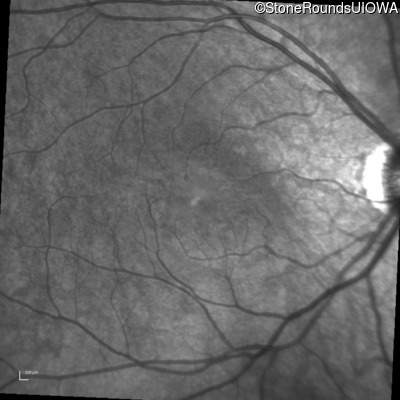

Infrared Fundus Photograph - Left - 20/50

Exemplar